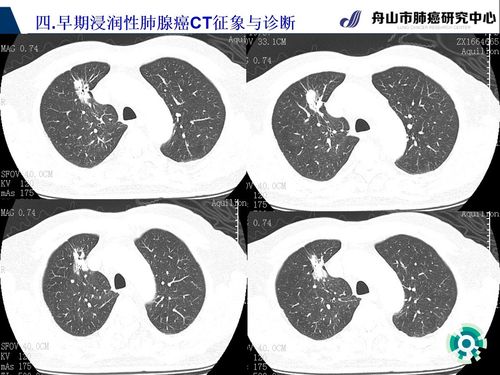

早期肺腺癌ct表现之早期浸润性肺腺癌